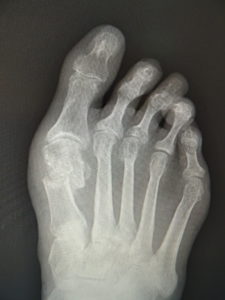

おおむね、外反角が30度以上になると、保存治療はもはやあまり有効ではありません。症状が強く、患者さんと良く吟味の上、希望されれば手術へと進みます。他に根治療法はないが、手術なら根治できます(図5)。ただMP関節の変性性変化があると、痛みや拘縮が残ることがあります。

(図5)

手術前 手術後4年

(図6)

手術前 手術後

(図7)

真田理事長による手術の様子。外反母趾|症例 (左から 手術前、手術後、ワイヤ抜去後)